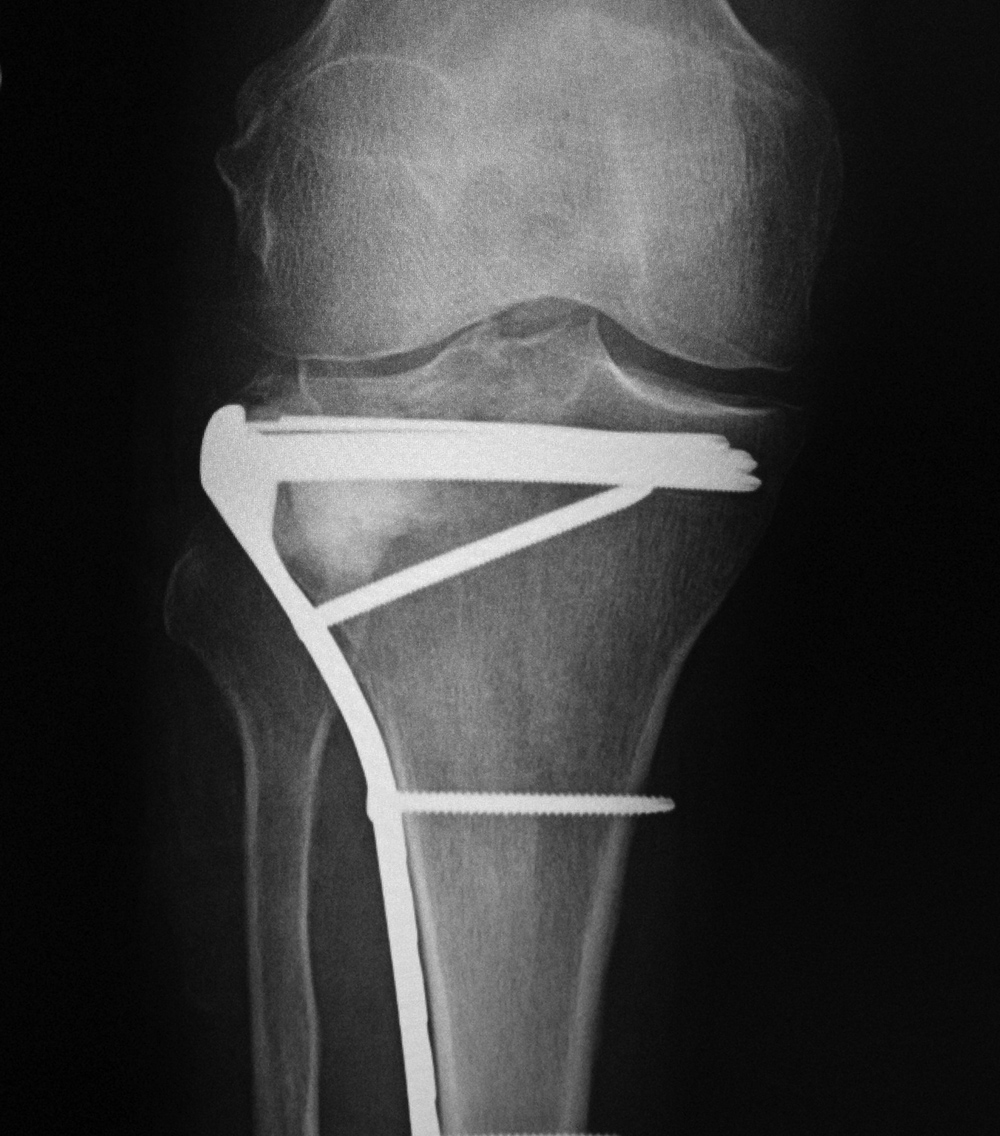

AP and lateral views of the knee show a distal femoral cadevaric limb sparing allograft approximated to the native distal femoral stump by a retrograde intramedullary nail. Two interlocking cannulated screws go through the distal portion of the nail. Cruciate ligament and capsular reattachment were performed with two interference screws and two staples in the proximal tibia and a staple in the posterior aspect of the allograft metaphysis. The patient had a non-specified distal femur sarcoma.